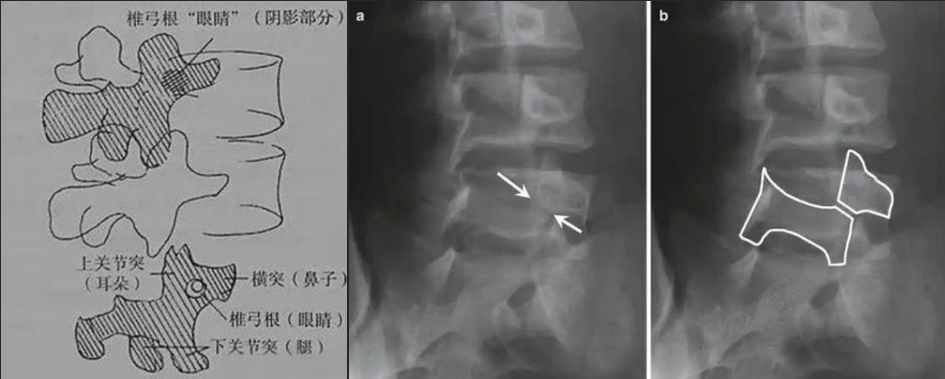

腰椎斜位片看什么?

如果說(shuō)腰椎正側(cè)位片是常規(guī)檢查體位,那么腰椎斜位片就是給腰椎的某個(gè)零件一張?zhí)貙戠R頭,這個(gè)特殊且關(guān)鍵的部位就是椎弓根峽部。

圖a和圖b 腰椎斜位:狗脖“戴項(xiàng)圈征”,診斷椎體椎弓峽部裂

椎弓根峽部是椎體后部椎弓上最狹窄、最薄弱、但應(yīng)力最集中的部位,在常規(guī)腰椎X線正側(cè)位上,因腰椎其他結(jié)構(gòu)的重疊顯示不清,但是在腰椎斜位上,能夠清楚完美地展現(xiàn)出來(lái),若其在斜位片上表現(xiàn)為不連續(xù),則可診斷為椎弓根峽部裂,即腰椎的關(guān)鍵承重部分的骨質(zhì)斷裂,這是導(dǎo)致青少年和運(yùn)動(dòng)員腰痛的主要原因。

在腰椎斜位片上,腰椎的附件結(jié)構(gòu)形成了一個(gè)經(jīng)典的“斯科蒂狗”圖案,其中“狗脖子”處即代表椎弓根峽部,若“狗脖子”上出現(xiàn)了一條透亮清晰的線,就像給狗戴了一條“項(xiàng)鏈”,即“戴項(xiàng)圈征”,這是診斷椎弓峽部裂的直接證據(jù)。